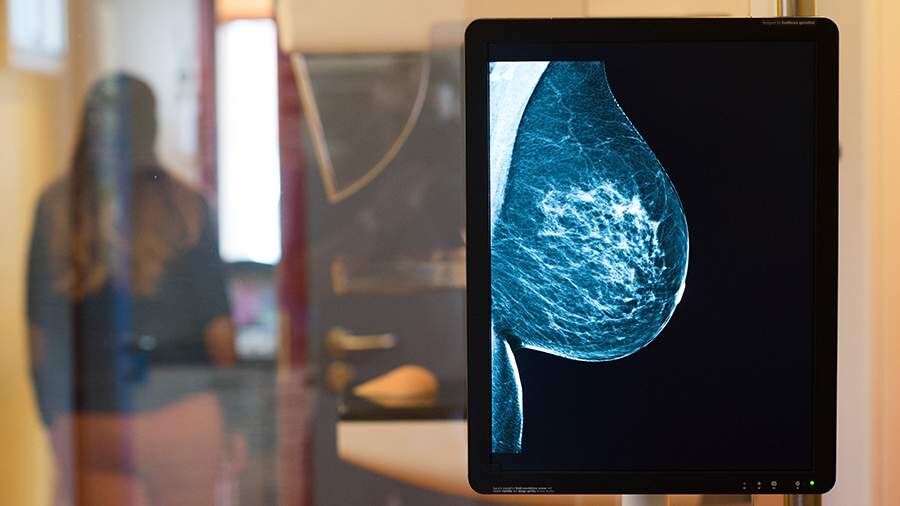

Фото: TASS/Klaus-Dietmar Gabbert

Рак молочной железы остается самым распространенным онкологическим заболеванием среди женщин, однако раннее выявление значительно повышает шансы на успешное лечение: до 98% пациенток полностью выздоравливают при диагностике на первой стадии. Об этом 8 декабря заявила «Известиям» врач-онколог, маммолог Елена Жукова.

Даже чувство распирания или покалывания в груди иногда сопровождает редкие воспалительные формы рака, при которых железа становится горячей, краснеет и болит. Однако Жукова подчеркнула, что на ранних стадиях заболевание зачастую протекает без симптомов, поэтому ежегодную диспансеризацию — УЗИ и маммографию — необходимо проходить каждой женщине, а осмотр маммолога должен стать регулярным.